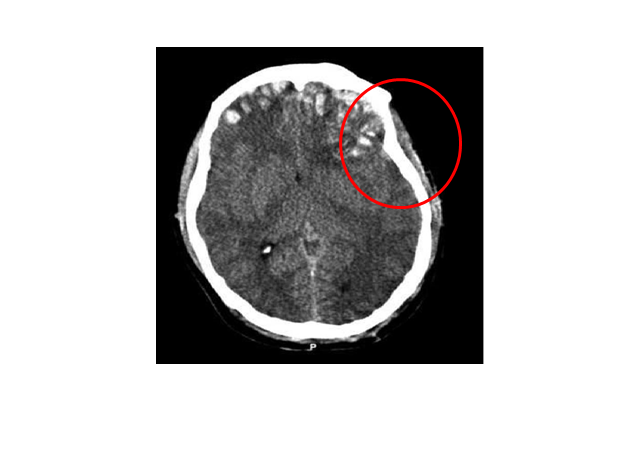

Plasticity that makes the brain vulnerable to injury: For one to remember an experience, the circuitry of the brain must change. Brain plasticity appears to be the physiological basis for the possibility of transforming our minds.